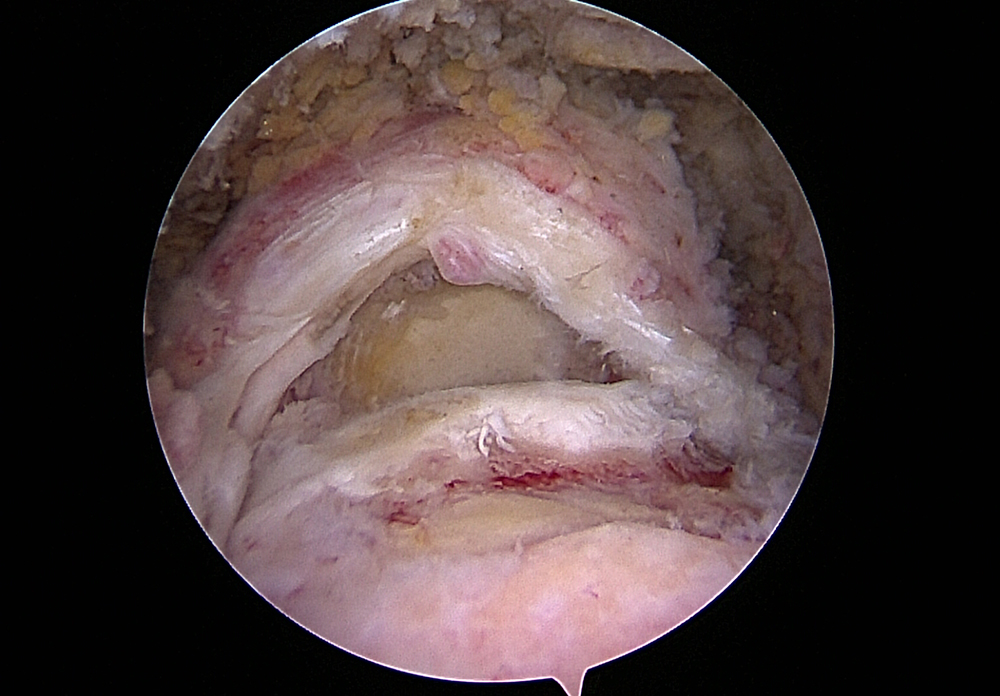

Grosser Riss Rotatorenmanschette